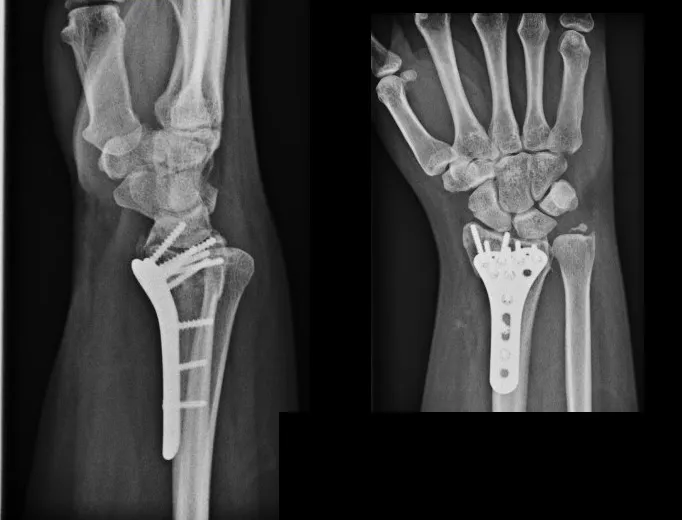

Leczenie operacyjne (dla III stopnia lub powikłanych urazów):

- W przypadku całkowitego zerwania więzadeł (III stopień), zwłaszcza u osób aktywnych fizycznie, może być konieczna operacja. Jej celem jest rekonstrukcja uszkodzonych więzadeł, aby przywrócić stabilność stawu.

- Po operacji również niezbędna jest intensywna rehabilitacja, która jest kluczowym elementem powrotu do pełnej sprawności. Bez niej nawet najlepiej przeprowadzona operacja nie przyniesie oczekiwanych rezultatów.